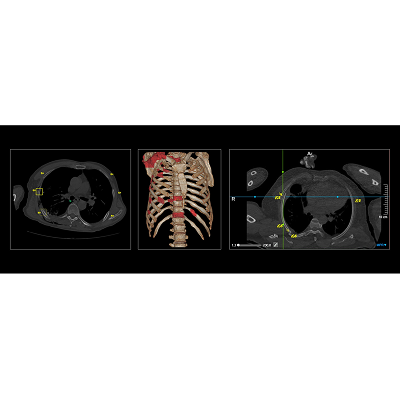

联影智能CT骨折智能分析系统具备“精确定位,秒级骨折检出,直观提示病灶,精细优化工作流”等一系列特点。基于深度学习的方法,自动完成肋骨、椎骨定位与计数,智能完成肋骨、椎骨、锁骨、肩胛骨、胸骨骨折检出与分类。同时,系统还提供MPR三视图、VR图、3D MIP、CPR、SCPR图像的全肋骨展开图、局部动态图等多种阅片视图,一键自动呈现骨折最佳视角,让骨折一目了然,细微骨伤“无处遁形”,辅助医生快速、高效、精准地完成骨折的诊断,避免错诊和漏诊。

上海市第六人民医院一个黄框,改变了我们的阅片习惯

上海六院是上海市骨科创伤中心,在2019中国医院影响力排行榜中,六院骨科排名全国前三。作为六院的优势学科,骨科影像检查占放射科业务量的一大部分,放射科每天诊断近百例肋骨骨折病例。 如今对于新的骨折病人,让CT骨折智能分析系统先跑一遍已成为上海六院放射科读肋骨骨折片时的习惯。目前,上海六院已通过联影智能CT骨折智能分析系统完成超过万例骨伤检测。